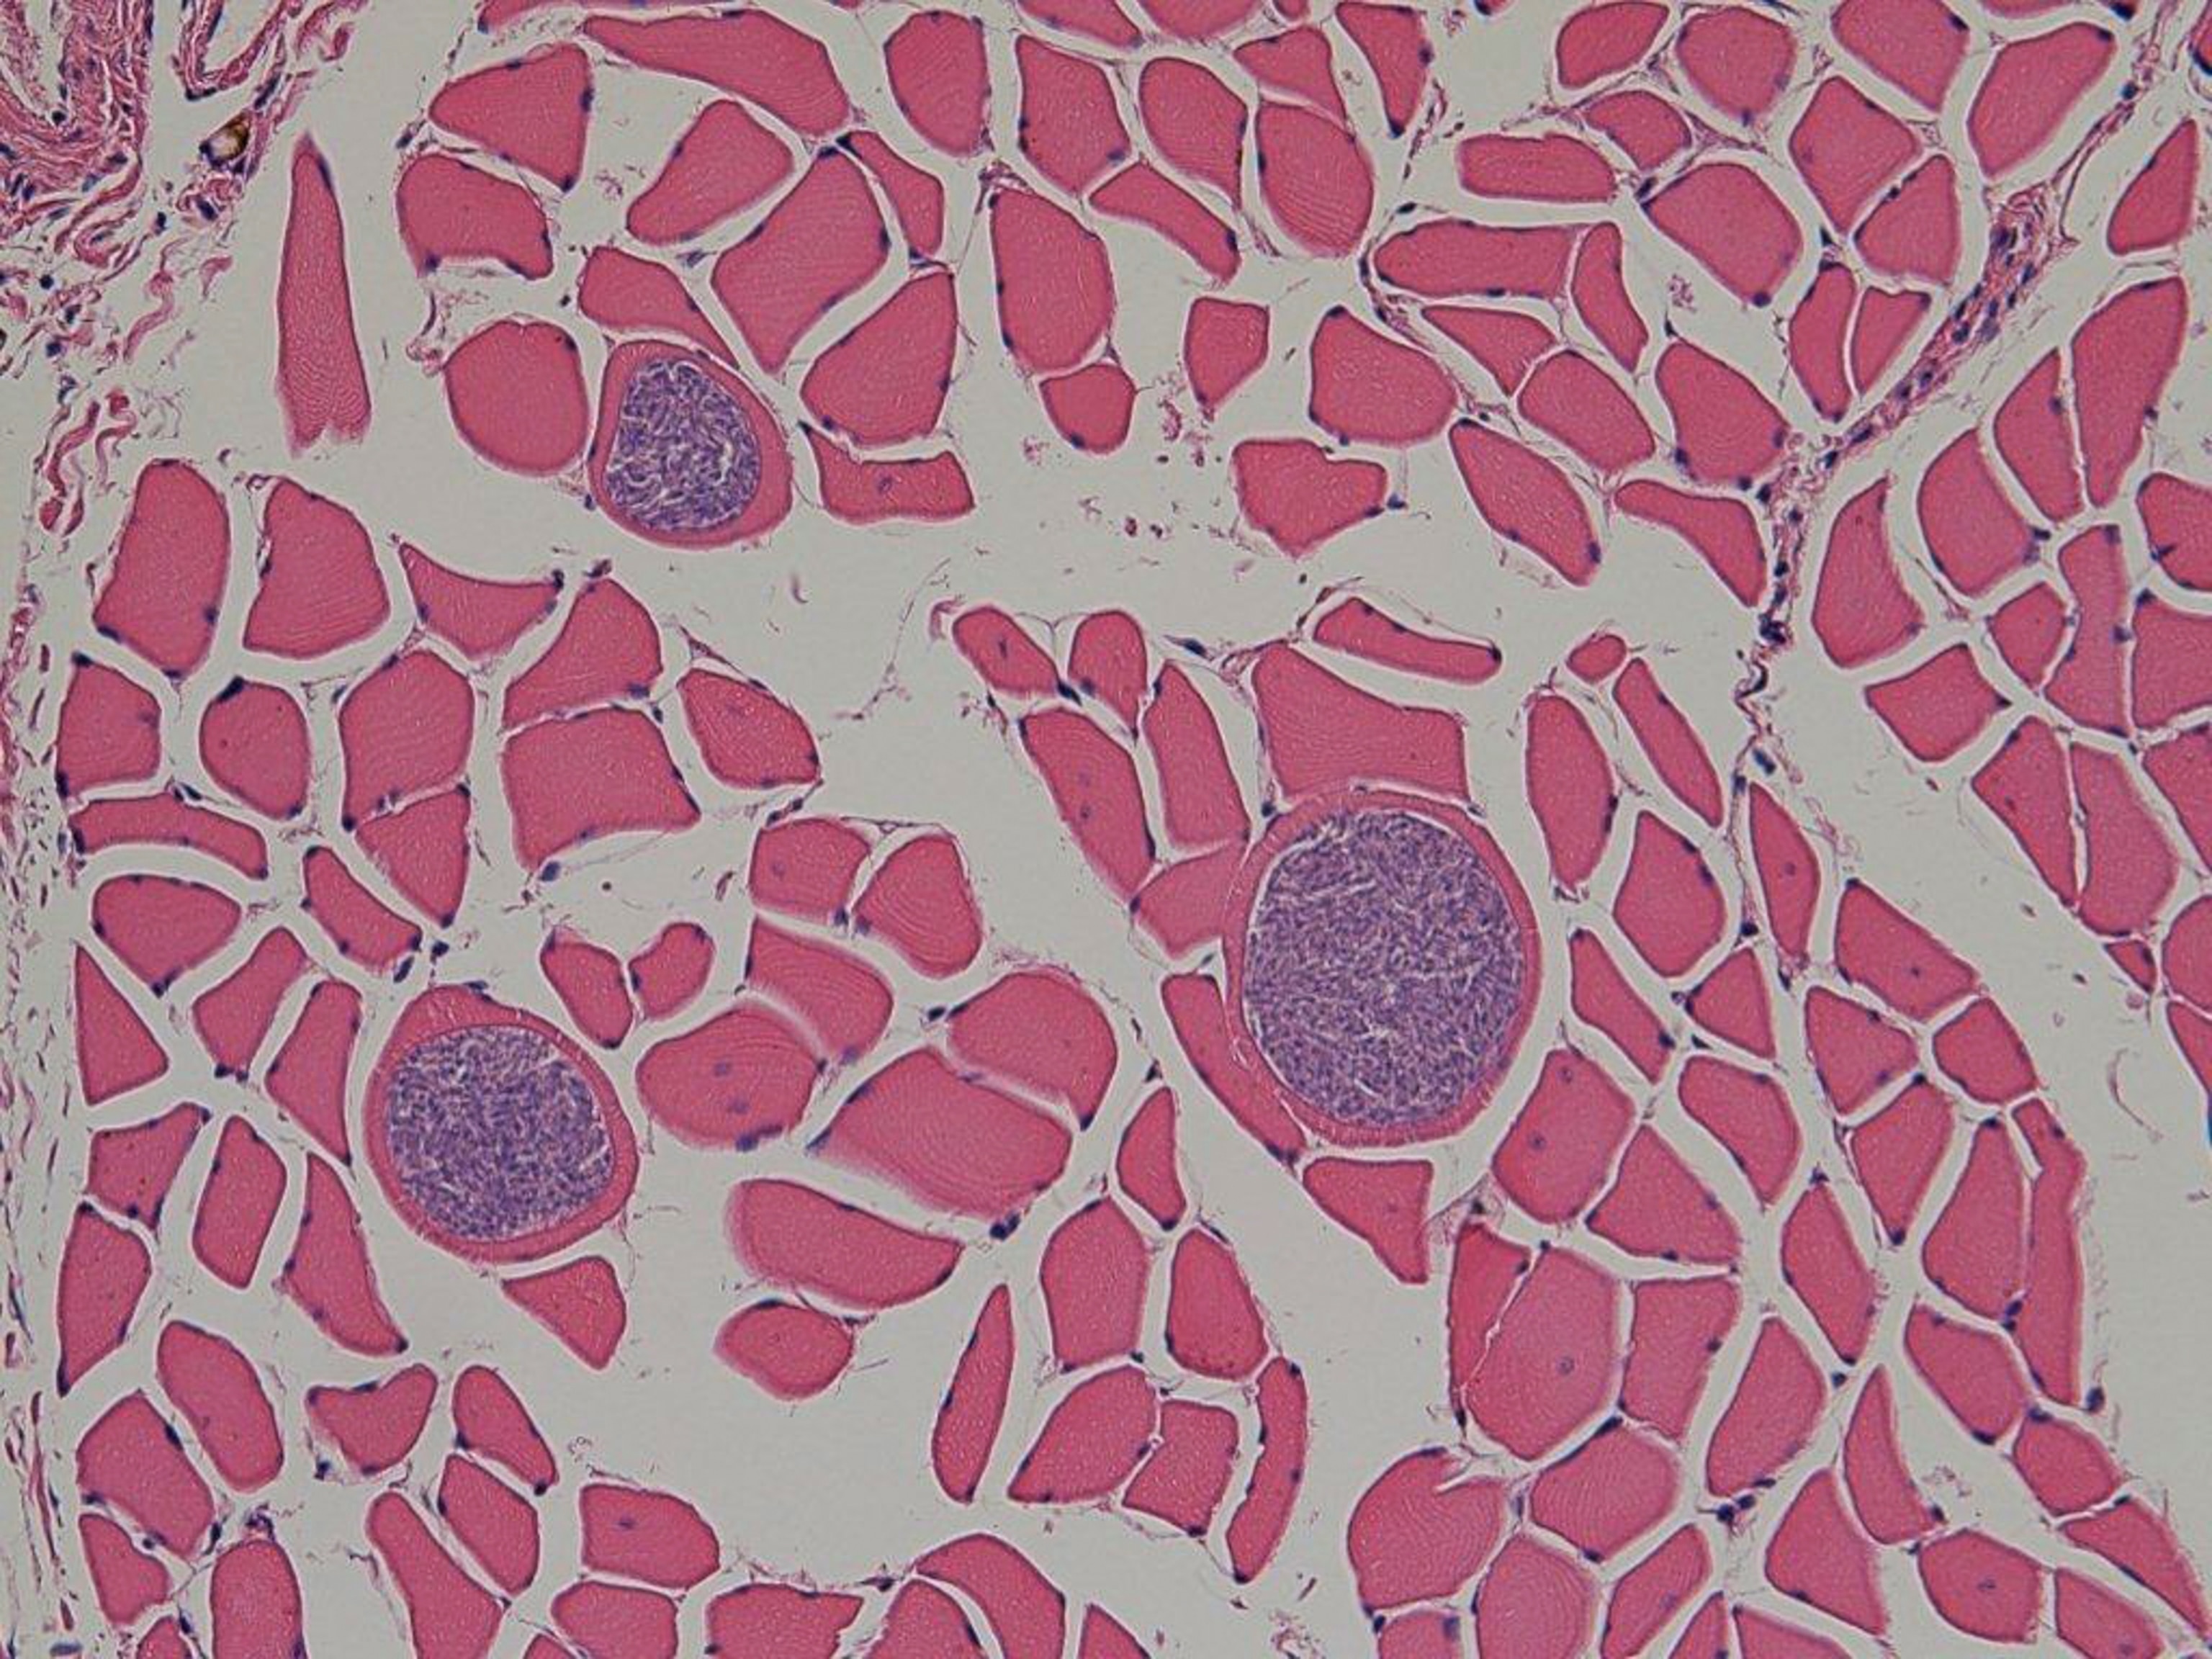

Experts face an equally challenging puzzle as a new parasite species—the crescent-shaped S. pinnipedi—emerges in gray seals.

And as both species pursue the same fish, S. pinnipedi can now move from its normal host—the ringed seal—into gray seals, which have never encountered it before.

The parasite acts like a cancer in gray seals, he explains. Normally, this kind of organism replicates inside a host until something tells it to switch to a slow-growing, cyst-forming stage that lets it infect its next host.

But that doesn't happen in gray seals. The parasite just keeps replicating in the liver until it completely destroys the organ. (Ringed seals have evolved to live with S. pinnipedi and don't seem to suffer the same fate.)